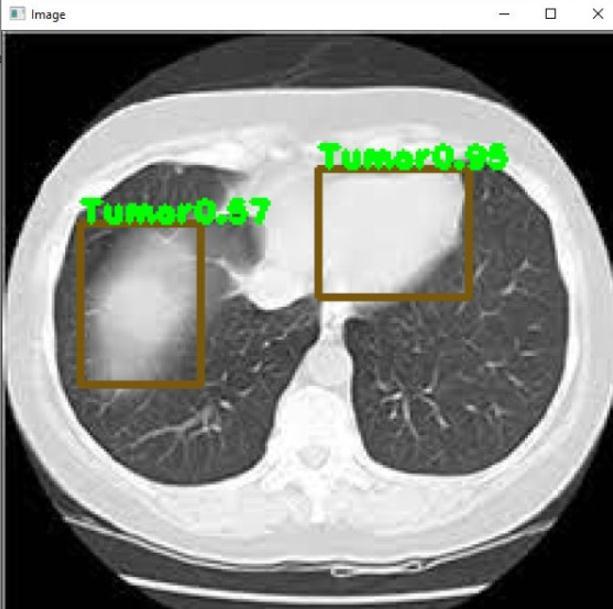

Fig 3 :TomorDetectedinLungs Fig 4 :ClotDetectioninLung Fig 4 :Clot&TumorDetectioninLung Fig – 5 :TumorDetectioninLung

finaloutcome.